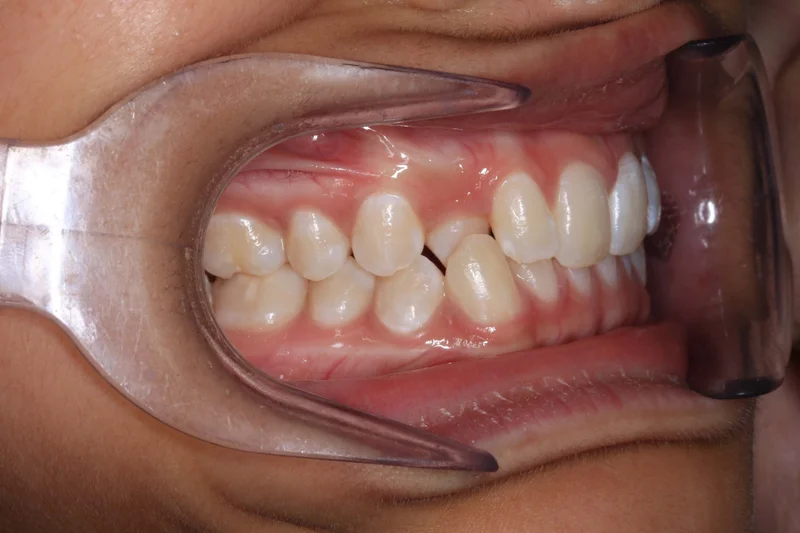

Right Buccal

Right Buccal - Before Treatment

Before

Right Buccal - After Treatment

After